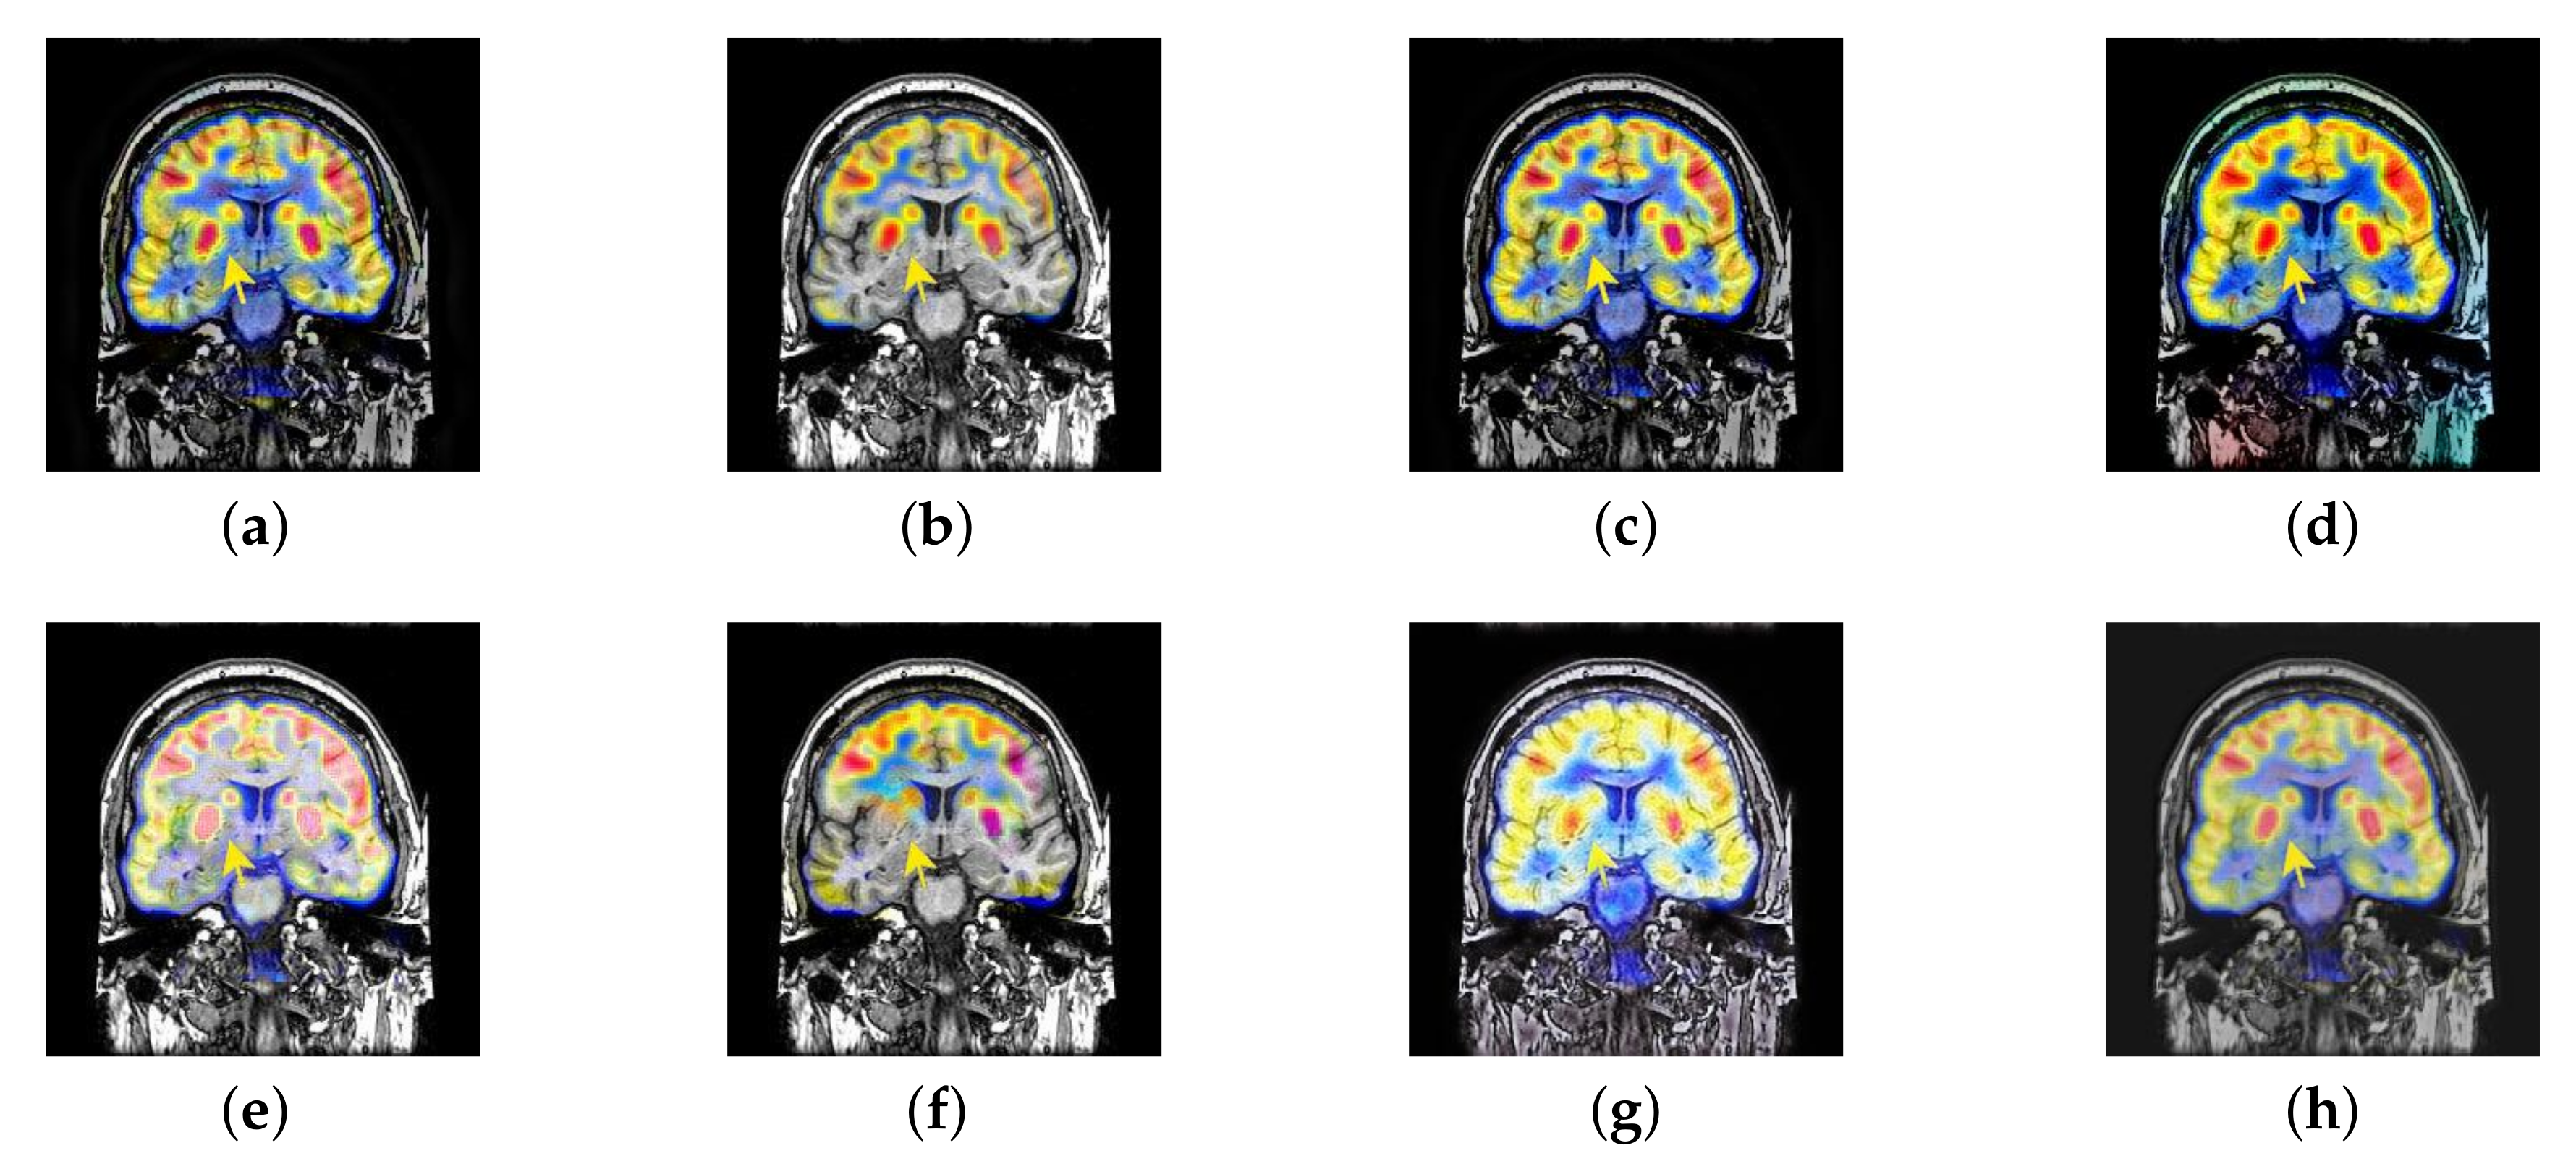

In this section, there are four multi-modal image sets and each set is consist of MRI image and SPECT image that are corresponding to the sanme location slice of the brain as shown in Figure 7. Among them, Figure 7e,f are captured from patients who have suffered a subacute stroke. Figure 7a–d,g,h are captured from patients who have brain tumor. The fused images with different fusion methods based on DTCWT, NSCT, GFF, LPSR, IGM, DDcGAN, FusionCNN, and the proposed methods are shown in Figure 8, Figure 9, Figure 10 and Figure 11. It can be seen that the fused images obtained by LPSR and FusionCNN algorithm have serious color distortion. Based on DTCWT and NSCT algorithm, the fusion image structure information is not obvious. The fused images obtained by GFF and IGM algorithm contain almost no color information, which is not conducive for doctors to make correct diagnosis. The image obtained by the DDcGAN algorithm saves the color information in the SPECT to a great extent; however, the brightness of the fused image is too large, which causes the image to have no sense of hierarchy and the contrast to decrease. By comparing with other algorithms, we find that our algorithm has good color retention effect, clear structure information, moderate brightness, and no artifacts.

Figure 8.

Fused medical images obtained by different algorithms (Figure 7a,b): (a) dual tree complex wavelet transform (DTCWT), (b) guided filtering fusion (GFF), (c) non-subsampled contourlet transform (NSCT), (d) Laplacian pyramid sparse representation (LPSR), (e) internal generative mechanism (IGM), (f) Fusion convolutional neural network based (FusionCNN), (g) dual-discriminator conditional generative adversarial network based (DDcGAN), and (h) FusionNet.

Figure 9.

Fused medical images obtained by different algorithms (Figure 7c,d): (a) DTCWT, (b) GFF, (c) NSCT, (d) LPSR, (e) IGM, (f) FusionCNN, (g) DDcGAN, and (h) FusionNet.

Figure 10.

Fused medical images obtained by different algorithms (Figure 7e,f): (a) DTCWT, (b) GFF, (c) NSCT, (d) LPSR, (e) IGM, (f) FusionCNN, (g) DDcGAN, and (h) FusionNet.

Figure 11.

Fused medical images obtained by different algorithms (Figure 7g,h): (a) DTCWT, (b) GFF, (c) NSCT, (d) LPSR, (e) IGM, (f) FusionCNN, (g) DDcGAN, and (h) FusionNet.